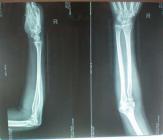

桡骨粉碎性骨折

手法正骨前 余**,女,55岁, 患者不慎摔倒损伤右手,后经拍片示:右桡骨粉碎性骨折伴右桡尺关节半脱位,医院建议手术治疗,患者不想手术,想中医保守冶疗,后经朋友介绍来诊,经本门诊特色手法整骨及夹板固定,再次拍片示,骨折对位对线良好已达98%以上。 手法正骨后[详情]